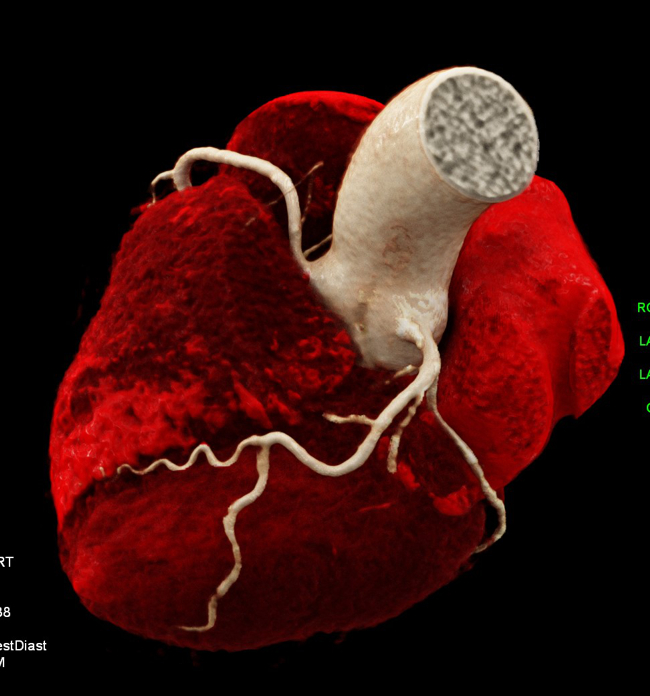

b) Structural heart disease CT for planning TAVR, TMVR and catheter ablation, including 3D printing, advanced 3D visualisation, congenital heart disease (Fig. 13).

CT: 10 Multicentre trials